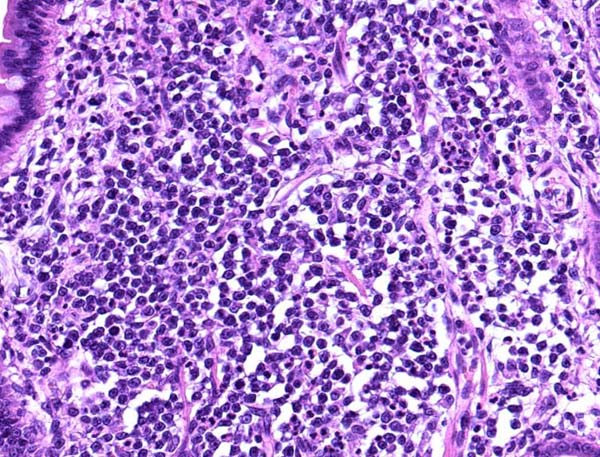

ワンちゃんが乳腺にできた複数のシコリを気にされて来院されました。bilateral mastectomyで対応しました。摘出後の病理組織検査の結果は、「R3-4間腫瘤:乳腺癌(複合型)」でそれ以外は「良性乳腺混合腫瘍」でした。無事元気に退院し、その後再発もなく経過は良好です。よかったね。